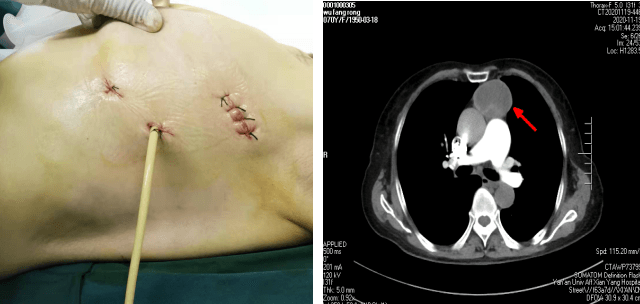

患者××,女,70歲,因“間斷腹部不適2月,加重10天” 于11月23日收入腫瘤/胸外科。胸部CT示前縱膈腫瘤。苗滿園主任帶領(lǐng)團(tuán)隊(duì)對(duì)該患者情況進(jìn)行了仔細(xì)的研究討論:縱膈腫瘤大小約10cm×6cm×6cm,邊界尚清,內(nèi)有鈣化,考慮良性腫瘤可能性大。與家屬溝通后選擇胸腔鏡下手術(shù)。手術(shù)團(tuán)隊(duì)經(jīng)精心術(shù)前準(zhǔn)備,于11月25日為患者實(shí)施全麻下“胸腔鏡下縱膈腫瘤切除術(shù)”。術(shù)中發(fā)現(xiàn)腫瘤起于心臟左前上方,經(jīng)主動(dòng)脈弓前達(dá)胸腔頂。術(shù)中仔細(xì)分離,克服因心臟跳動(dòng)及主動(dòng)脈搏動(dòng)的不穩(wěn)定性,保護(hù)好心臟、膈神經(jīng)、主動(dòng)脈,出血量少,手術(shù)十分順利,歷時(shí)1小時(shí),完整切除腫瘤。嚴(yán)格按圍手術(shù)期ERAS管道管理改進(jìn)措施,選用留置導(dǎo)尿管單根引流,避免傳統(tǒng)手術(shù)因引流管粗硬導(dǎo)致的術(shù)后疼痛不適,術(shù)后當(dāng)天即可獨(dú)立下床活動(dòng),生活完全自理?;颊呒凹覍俜浅M意,極大地提高了患者的就醫(yī)體驗(yàn)。